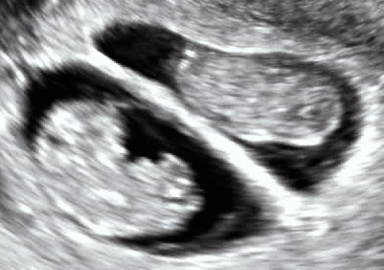

Twins are two offspring produced by the same pregnancy.[1] Twins can be either monozygotic ("identical"), meaning that they develop from one zygote, which splits and forms two embryos, or dizygotic ("fraternal"), meaning that they develop from two different eggs. In fraternal twins, each twin is fertilized by its own sperm cell.[2]

Monozygotic (MZ) or identical twins occur when a single egg is fertilized to form one zygote (hence, "monozygotic") which then divides into two separate embryos.

The degree of separation of the twins in utero depends on if and when they split into two zygotes. Dizygotic twins were always two zygotes. Monozygotic twins split into two zygotes at some time very early in the pregnancy. The timing of this separation determines the chorionicity (the number of placentae) and amniocity (the number of sacs) of the pregnancy. Dichorionic twins either never divided (i.e.: were dizygotic) or they divided within the first 4 days. Monoamnionic twins divide after the first week.